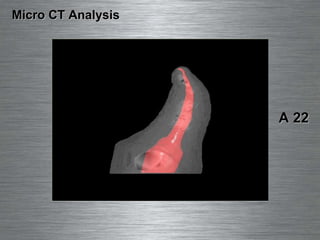

Micro CT Analysis A 22